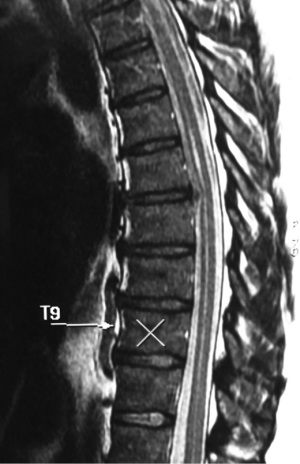

A 74-year-old male presented with a 12-month history of progressive low back pain (VAS 8/10) with an inability to stand for more than 10 minutes or participate in recreational activities. No neurologic deficit was revealed on initial examination, comorbidities included hypertension and prior history of tobacco use. Preoperative CT thoracolumbar scan demonstrated multilevel degenerative disc disease (DDD) most marked at T12-L1 with a degenerative grade I spondylolisthesis at L3-4 (Figure 6). Isotope Tc99m bone scan coregistered with CT showed radiotracer uptake mainly at T12-L1 disc level and lesser extent at L3-4 disc and L5-S1 facet joints. The patient was unresponsive to opiate analgesia, CT guided facet joint or transforaminal epidural nerve root injections. The patient underwent a left retropleural transdiaphragmatic T12-L1 LIF with an interbody cage (8×18×45 mm3, zero degree, CoRoent XL-T). EBL was less than 50 mL. A 24 gauge intercostal drain was placed intraoperatively and removed 24 hours postoperatively. Postoperative CT demonstrated satisfactory prosthesis placement at T12-L1. The patient was discharged to home on day 5. He ceased all analgesia and returned to normal work duties 5 weeks postoperatively. A solid fusion was confirmed on CT at 12 months (Figure 7). The patient reported improvements in low back pain (VAS 8/10 to 2/10), ODI (38 to 20), PCS (33 to 40) and MCS (46 to 52) at 24 month follow-up.